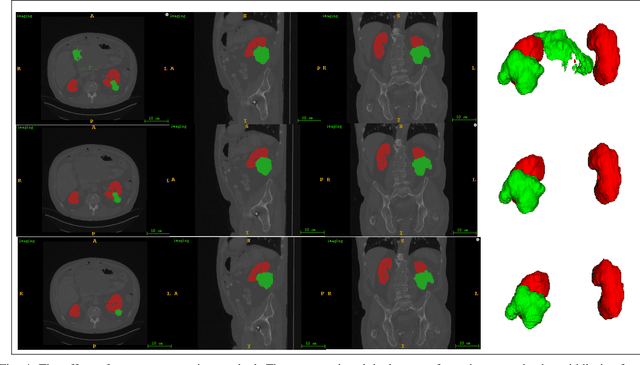

Abstract:Accurate segmentation of kidneys and kidney tumors is an essential step for radiomic analysis as well as developing advanced surgical planning techniques. In clinical analysis, the segmentation is currently performed by clinicians from the visual inspection images gathered through a computed tomography (CT) scan. This process is laborious and its success significantly depends on previous experience. Moreover, the uncertainty in the tumor location and heterogeneity of scans across patients increases the error rate. To tackle this issue, computer-aided segmentation based on deep learning techniques have become increasingly popular. We present a multi-scale supervised 3D U-Net, MSS U-Net, to automatically segment kidneys and kidney tumors from CT images. Our architecture combines deep supervision with exponential logarithmic loss to increase the 3D U-Net training efficiency. Furthermore, we introduce a connected-component based post processing method to enhance the performance of the overall process. This architecture shows superior performance compared to state-of-the-art works using data from KiTS19 public dataset, with the Dice coefficient of kidney and tumor up to 0.969 and 0.805 respectively. The segmentation techniques introduced in this paper have been tested in the KiTS19 challenge with its corresponding dataset.